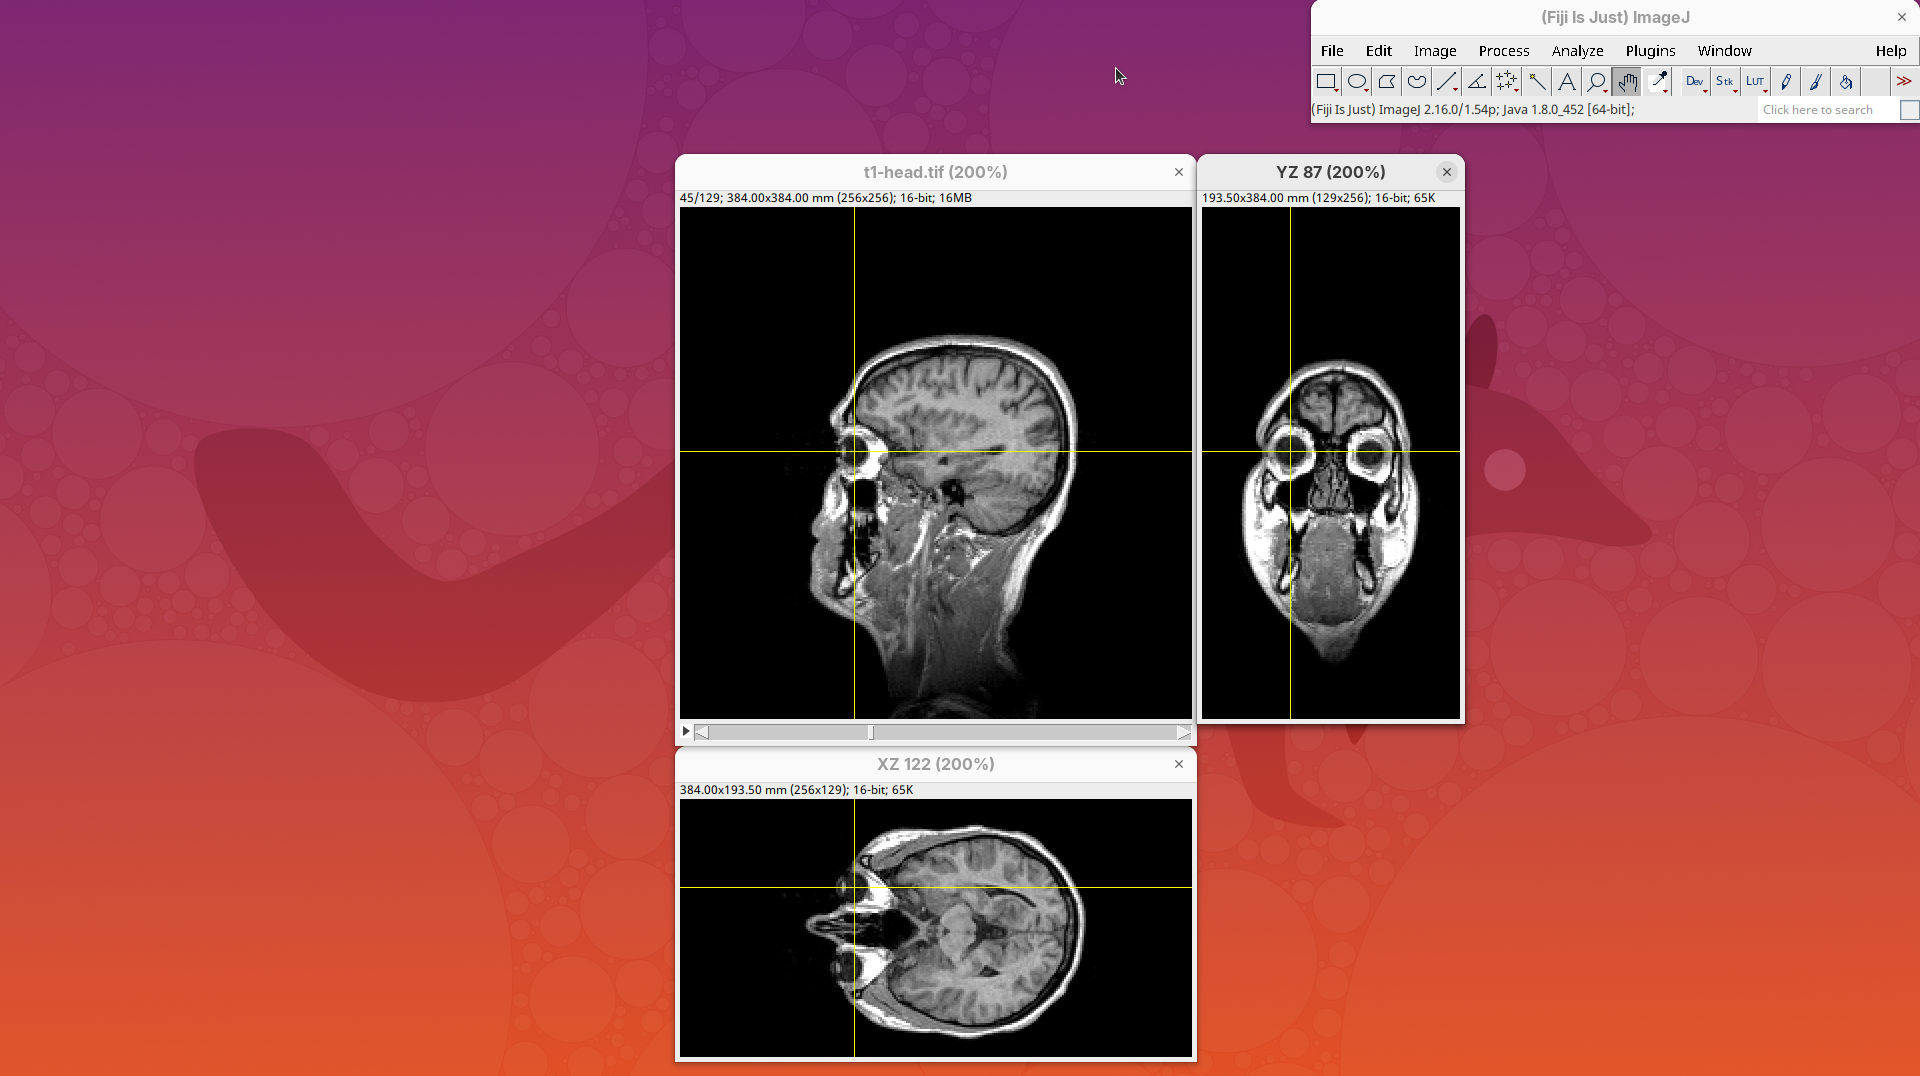

Volume Viewer

Volume Viewer is a more powerful plugin for 3D visualization as it supports slicing, projections, and rendering. The interface is interactive and intuitive to use. To open it:

- Go to

Plugins>Volume Viewer. The main interface will open in theSlicemode.

- Click around and move the sample to see optical sections from different angles.

- Then, activate the

Volumemode to render the sample’s surface in 3D and explore it as well, playing with the different rendering parameters.

Volume Viewer also provides a way to take snapshots of the current view.